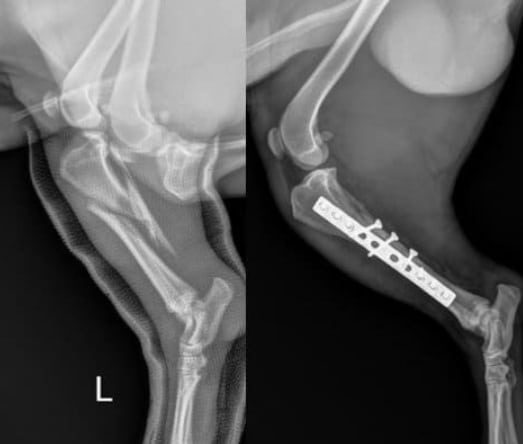

Fractures can be diagnosed in two different ways. The first thing is to see with the eyes. Vets have the experience and can tell which bone is fractured by looking. If the fracture is incomplete and the bone is not seen, imaging technology and radiology are used to take X-rays of the injured area. The CT scans will tell the right bone and fracture type in the dogs to provide the relevant treatment.

Non-surgical procedures do not require the use of tools to pierce through the bone and fix the issue. It can be done easily with the casts or splints. It is monitored regularly with X-rays to avoid any issues.

Surgical procedures involve the use of tools to fix the bones with the help of plates or screws. Other medical equipment is used to give proper alignment to the bones. This helps in the proper functioning and healing of the fracture.